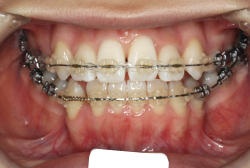

上顎前突

上顎前突(出っ歯)とは上顎が前に出ている状態です。この症状の特徴は、上下の歯並び全体の位置関係が相対的に上顎が優位になっていて、前歯が外に反っているだけでなく奥歯の位置関係も上が前にズレています。さらに凸凹の症状も合併していることがよくあり、上の前歯の見た目を気にして来院する方が多いのですが、実は今言った理由で噛み合わせにも異常があるため、このまま放置すると顎関節症という症状が出ることもあります。

「出っ歯を治したい」という主訴で来院したケースです。診断の結果、「2級1類の上顎前突+軽度叢生」と判明しました。2級というのは、基本的に出っ歯の噛み合わせになっていることを言います。その中でも上の前歯が著しく外に反っているケースを、「1類」といいます。初診時の横向きの写真を見ると、それがはっきり分かります。上の前歯に押されて唇も膨らんで、審美線をかなりオーバーしています(審美線とは、鼻の先端と顎の先端を結ぶ線のことで、この線よりも唇は内側にある方が良いとされています)。

このような症状の場合は、前歯を内側に入れるためにかなり大量の隙間を必要とします。通常は上下左右の小臼歯を抜歯させていただくのが正解です。治療後は歯の角度が正しくなっただけでなく、唇の審美性が大幅に改善しました。もちろん噛み合わせ的にも正しい状態が確立しています。